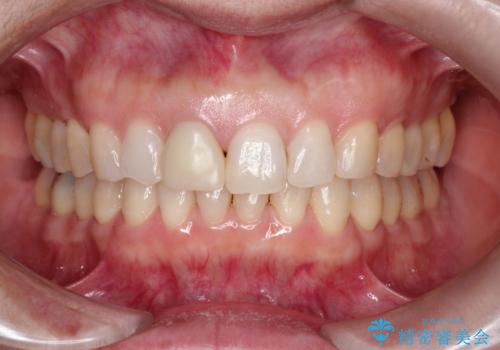

- 「他院で治療した前歯の被せものが一か月の間に2回外れたのでやり変えたい」を主訴に来院されました。

10年前に根管治療を他院で行っており、根尖性歯周炎の予防のため根管治療から行いました。被せものはオールセラミッククラウンで治療を行いました。

ホワイトニングもご希望されたのでホームホワイトニングも行いました。

10年前にラバーダムシート無しに根管治療を行っており、現在、症状は出ていませんが、根尖性歯周炎の予防のため根管治療から行いました。ホームホワイトニングを2週間行って頂き、その後、オールセラミッククラウンで治療を行っています。